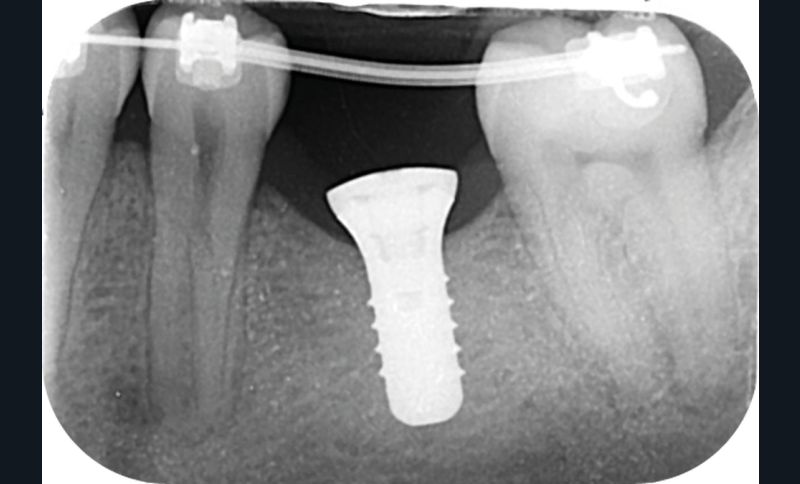

La prise en charge de ces édentements nécessite un examen complet du site implantaire et de l’environnement [16]. Les conséquences du non-remplacement rapide que nous venons d’énumérer sont à prendre en compte et à corriger pour une intégration optimale de la restauration prothétique implantaire. Ainsi, des corrections orthodontiques peuvent être nécessaires avant ou pendant la thérapeutique implantaire.

Le temps de l’ostéointégration, des versions ou migrations sont aussi possibles et le recours à des dispositifs de maintien de l’espace peut se révéler indispensable (fig. 22 et 23).